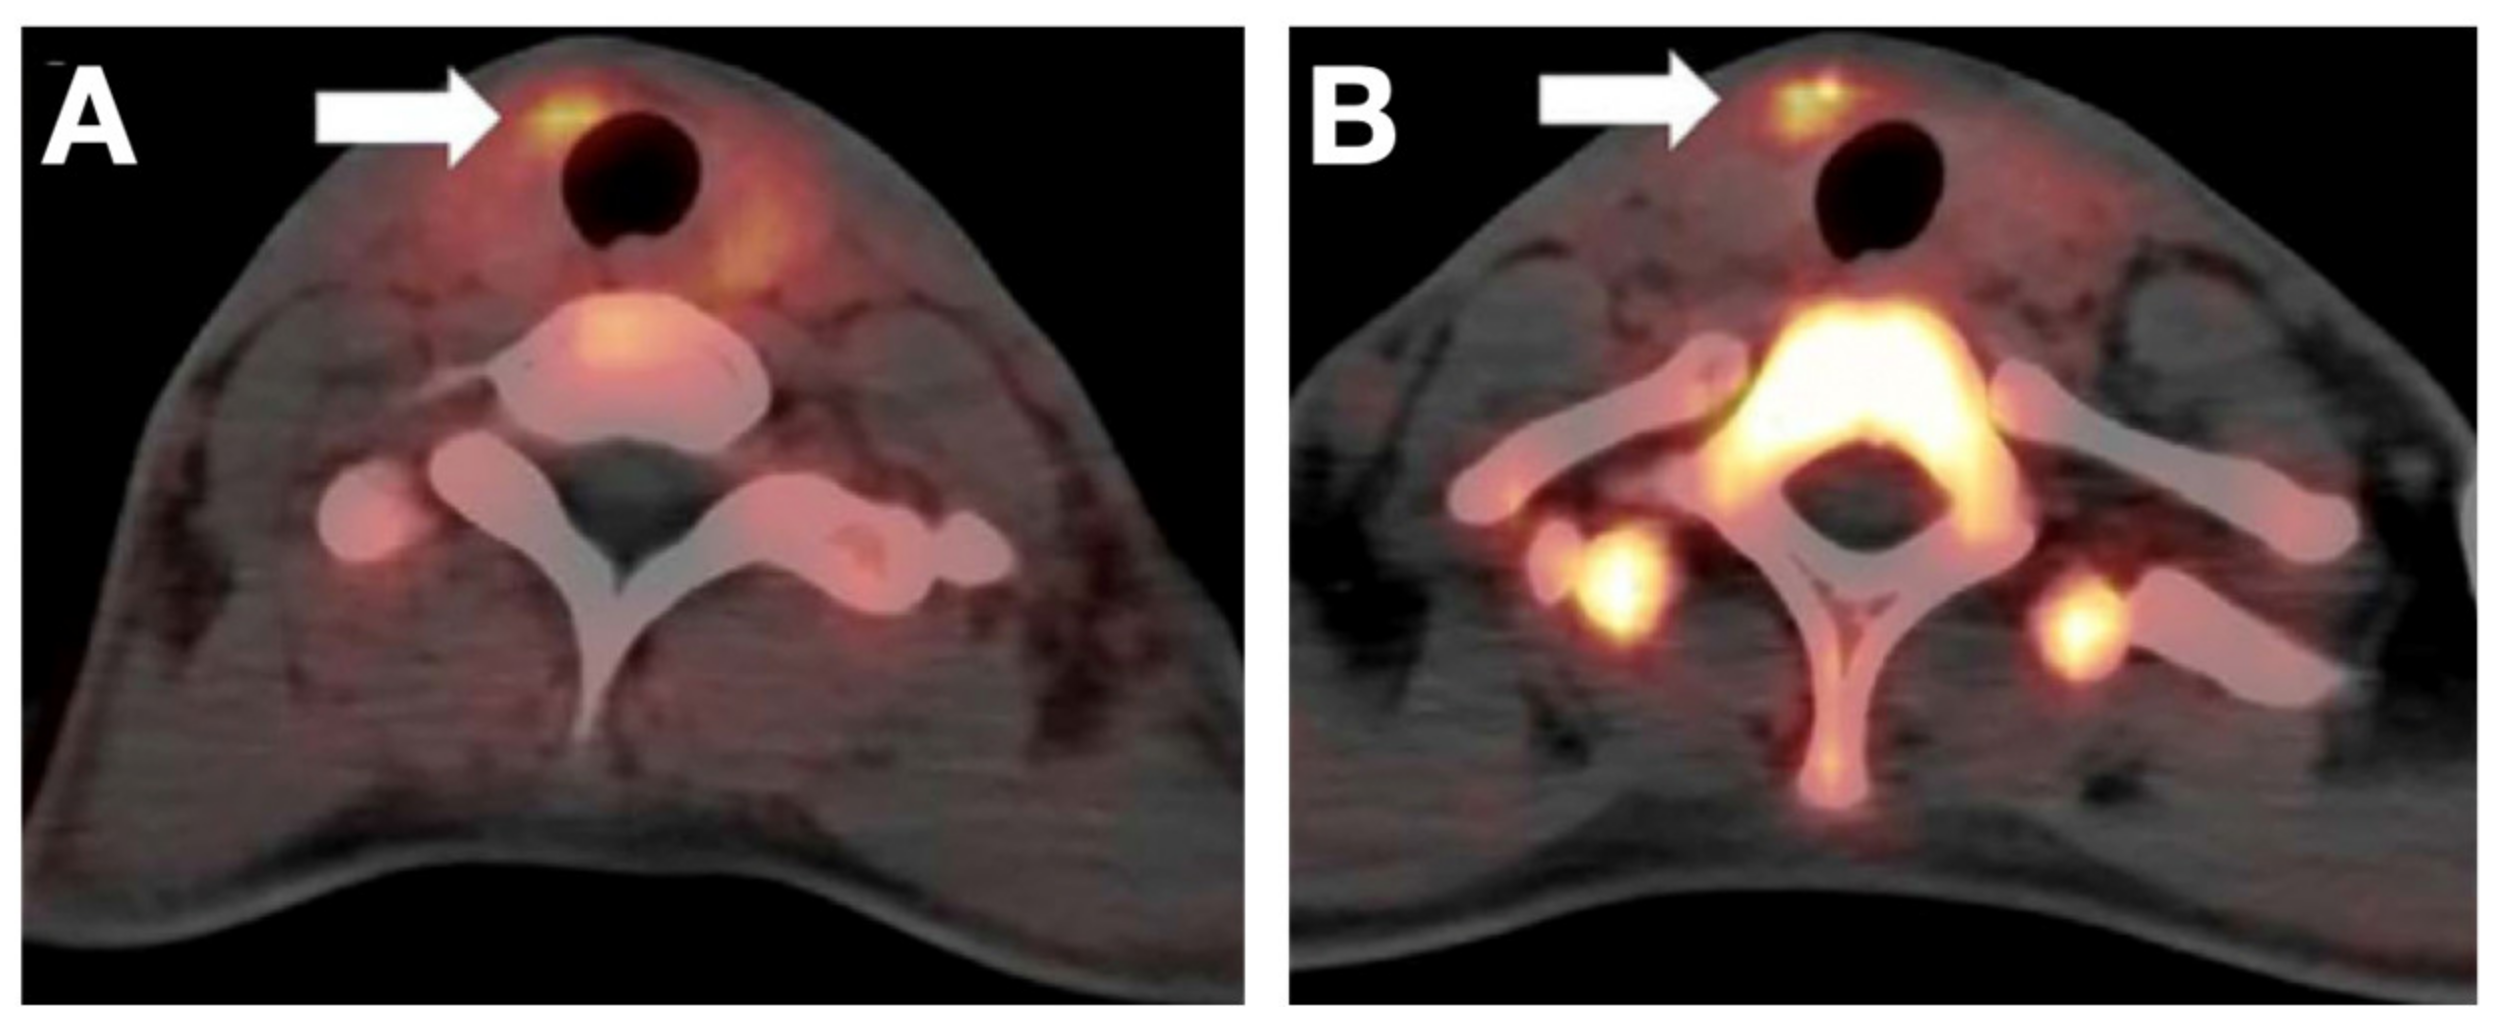

- Samnick, S.; Al-Momani, E.; Schmid, J.-S.; Mottok, A.; Buck, A.K.; Lapa, C. Initial Clinical Investigation of [18F]Tetrafluoroborate PET/CT in Comparison to [124I]Iodine PET/CT for Imaging Thyroid Cancer. Clin. Nucl. Med. 2018, 43, 162–167. [Google Scholar] [CrossRef]